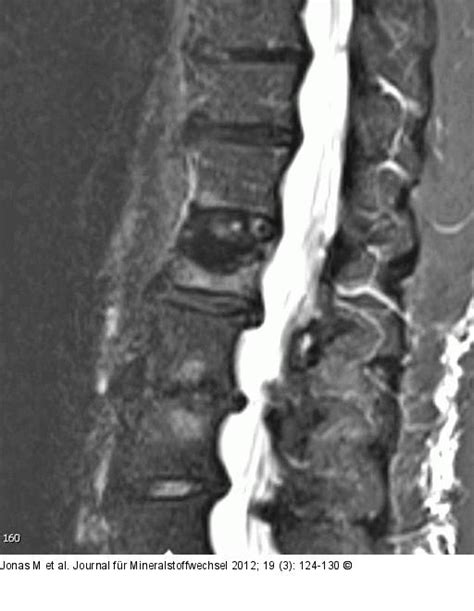

Diagnosis usually starts with a detailed medical history and a physical examination. Your doctor will ask about your symptoms, when they started, and what makes them better or worse. They’ll also perform a physical exam to assess your range of motion, check for tenderness, and evaluate your neurological function. Imaging tests play a vital role in confirming the diagnosis. X-rays are often the first step, as they can reveal compression fractures. However, they may not always show the full extent of the damage. More advanced imaging techniques, such as MRI and CT scans, provide more detailed views of the spine and can help determine the severity of the fracture, identify any nerve compression, and rule out other possible causes of pain, such as tumors or infections. These scans allow healthcare professionals to visualize the bones, soft tissues, and spinal cord, providing a comprehensive understanding of the injury. The information gained from these scans helps the doctor make an accurate diagnosis and develop an appropriate treatment plan.